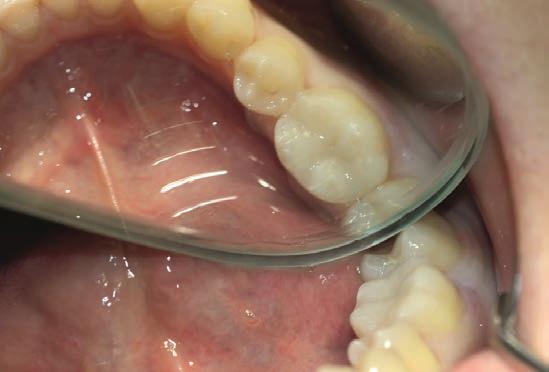

Figure 3: Final result: a natural-looking aesthetic restoration

The composite Polofil NHT was then applied in shade A3 in 2 mm increments and every layer was light-cured for 20 seconds with a light output of 500 mW/cm2.

After modelling the occlusal surface the occlusal contacts were checked, followed by finishing with a diamond polisher with a small tip, as well as polishing with paper and silicone grinding burrs.

Finally, a varnish containing fluoride (Bifluorid 12, VOCO) was applied to seal the restoration margins with fluorides. The result shows a natural-looking restoration, the colouring of which also harmonises perfectly with the natural tooth substance.